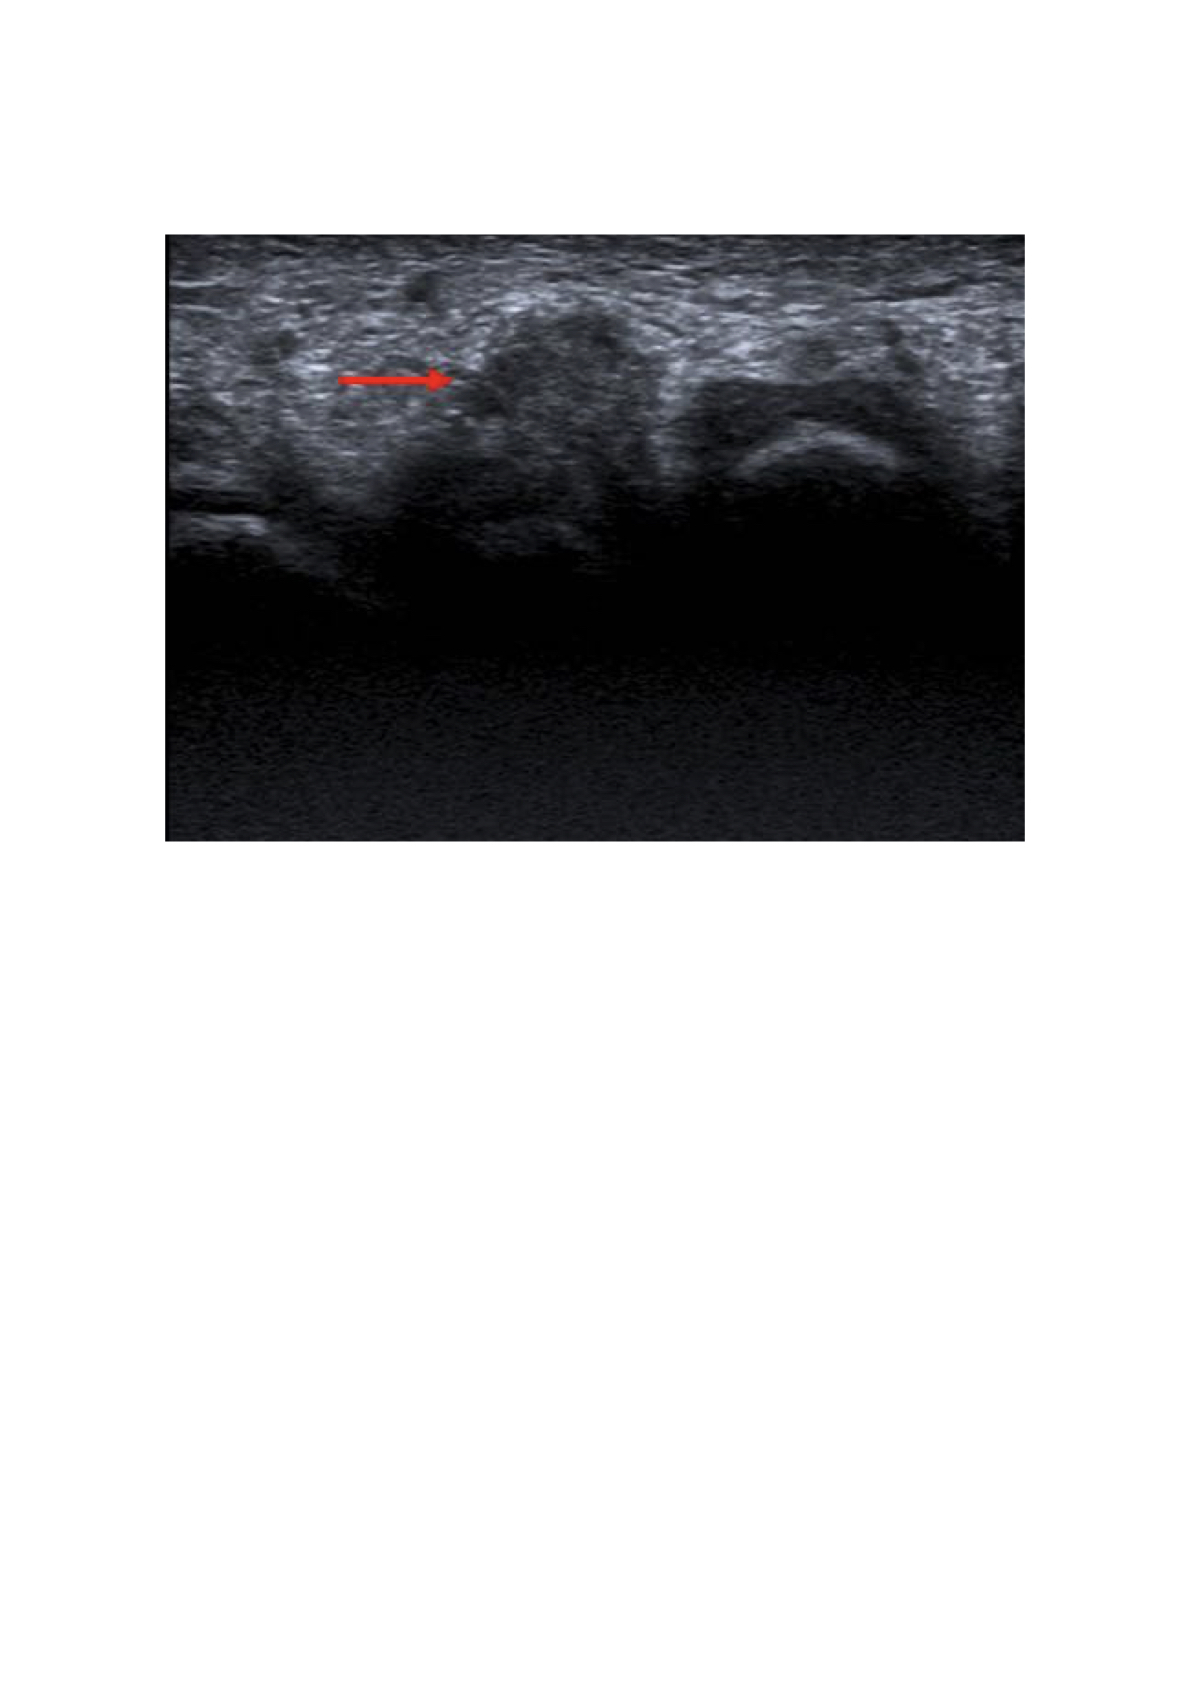

En corte transversal por acceso plantar se identifica una masa hipoecoica redondeada homogénea de bordes bien definidos en tercer espacio interdigital de 7 mm, compatible con neuroma de Morton.

A la compresión lateral existe una extrusión hacia la planta del pie.